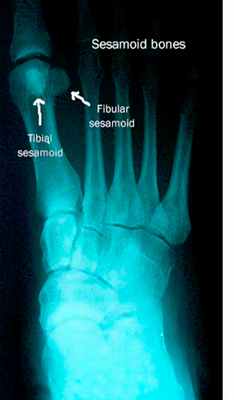

Рис. 2. Рентгенограмма правой стопы. По внутреннему краю расположена большеберцовая или медиальная сесамовидная кость, по наружному краю – малоберцовая или латеральная сесамовидная кость